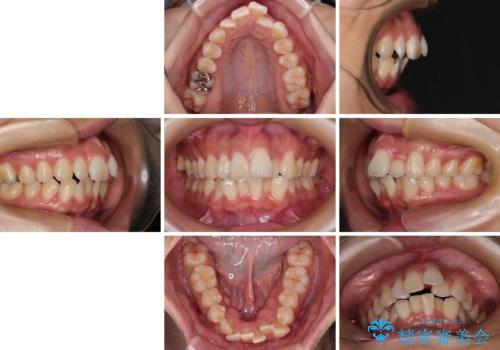

- 上下の出っ歯を気にして来院された患者様です。

口元を積極的に引っ込めるために、上下左右の第一小臼歯を4本抜歯することとしました。

下顎の正中を上顎に合わせる処置が難航し、期間が長引きました。

最終的には上下の正中も合い、横顔の印象が変わるほどスッキリとした口元となりました。